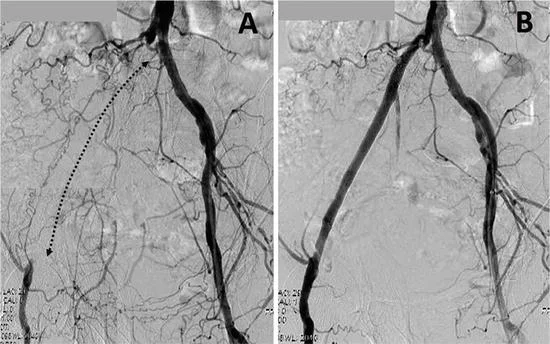

Anjiyografi: Arteriyogram olarak da adlandırılan bir anjiyogram sırasında, artere bir kontrast madde enjekte edilir ve kan akışını, bacaklardaki atardamarları göstermek ve mevcut olabilecek herhangi bir tıkanıklığı belirlemek için görüntüler alınır.

Ameliyatsız, girişimsel Yöntemler (Endovasküler Yöntemler)

Ayaklarında iyileşmeyen yaraları olan ve istirahat ağrısı olan hastalar ile bacağının kesilmesi (amputasyon) planlanan ancak amputasyon seviyesinin daha aşağıdan olması için uğraşılan hastalarda kullanılması gereken ilk basamak işlemlerdir. Girişimsel yöntemler ile cerrahi arasındaki seçim darlığın yeri, uzunluğu, damar yapısı ve hastanın genel durumu değerlendirilerek yapılır.

Girişimsel yöntemlerin hepsi anjiografi salonunda, lokal anestez altında ve herhangi bir kesi yapılmadan uygulanır. Hastanede yatış süresi ve iyileşme süreci, cerrahi tedaviye göre daha kısadır. Bununla birlikte işlem yapılan damarlarda erken veya geç dönemde tekrar darlık oluşma veya tıkanma riski bulunmaktadır.

Tıkanıklığın veya darlığın yerine, uzunluğuna ve süresine bağlı olarak aşağıdaki işlemlerden biri veya birkaçı kombine edilerek kullanılabilir.